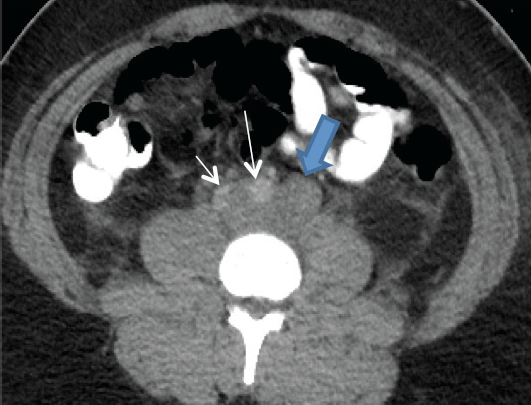

Figure 2. Axial computed tomography image, at a level just above aortic bifurcation, showing a large retroperitoneal mass (large blue arrow) displacing and partially encasing the aorta (long thin arrow) and inferior vena cava (short thin arrow).

Computed tomography (CT) scans (Figure 1) revealed a retroperitoneal mass infiltrating the genitourinary system, causing external compression of the left ureter and displacing and partially encasing the aorta and inferior vena cava. CT scans also revealed a large metastatic retroperitoneal lymph node displacing the left renal vein anteriorly (Figure 2).